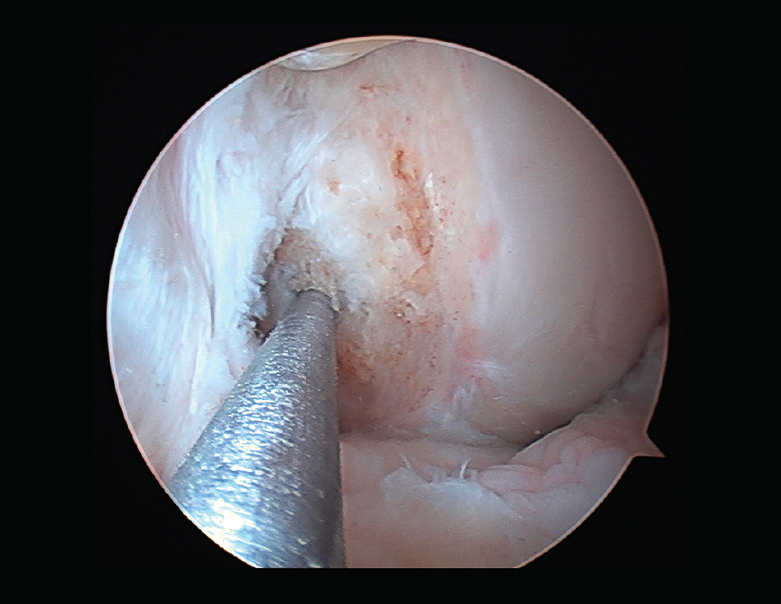

Rigidez

Una de las complicaciones más temidas, producida por un aumento del tejido fibroso, ya sea por la propia lesión (primaria) o secundaria a diferentes motivos (error técnico en la cirugía, síndrome del cíclope, inmovilización prolongada o la participación insuficiente en un programa de rehabilitación, infección, síndrome del dolor regional complejo, hematomas o sinovitis) (Figuras 7 y 8). Esta puede variar desde una ligera limitación del rango de movilidad hasta una severa artrofibrosis(21).

Las principales causas secundarias a errores técnicos son la malposición de la plastia y el tensado excesivo. La radiografía permite ver la localización de los túneles e implantes, así como la RM visualiza las partes blandas implicadas, pudiendo identificar posibles pinzamientos de la plastia –escotadura intercondílea, síndrome del cíclope (Figura 9), síndrome de la contractura infrapatelar(22)(Figura 10)–.

Figura 9. Cíclope, tejido fibroso interpuesto en la cara anterior de la plastia y que produce pinzamiento de la misma en extensión de rodilla.

La cronología tras la cirugía es también importante. Durante los 3 primeros meses tras la intervención podemos tratar satisfactoriamente rigideces menores con rehabilitación, antiinflamatorios no esteroideos (AINE) y manipulación. Más allá de los 4 meses, se recomienda desbridamiento artroscópico. No se recomienda la manipulación bajo anestesia sin una liberación articular artroscópica del tejido cicatricial. El desbridamiento artroscópico incluye la retirada de tejido cicatricial, grasa de Hoffa, liberación cuadricipital de la cara anterior femoral y de los recesos laterales, y ocasionalmente liberación de retináculos patelares si la movilidad patelar fuera insuficiente(23).